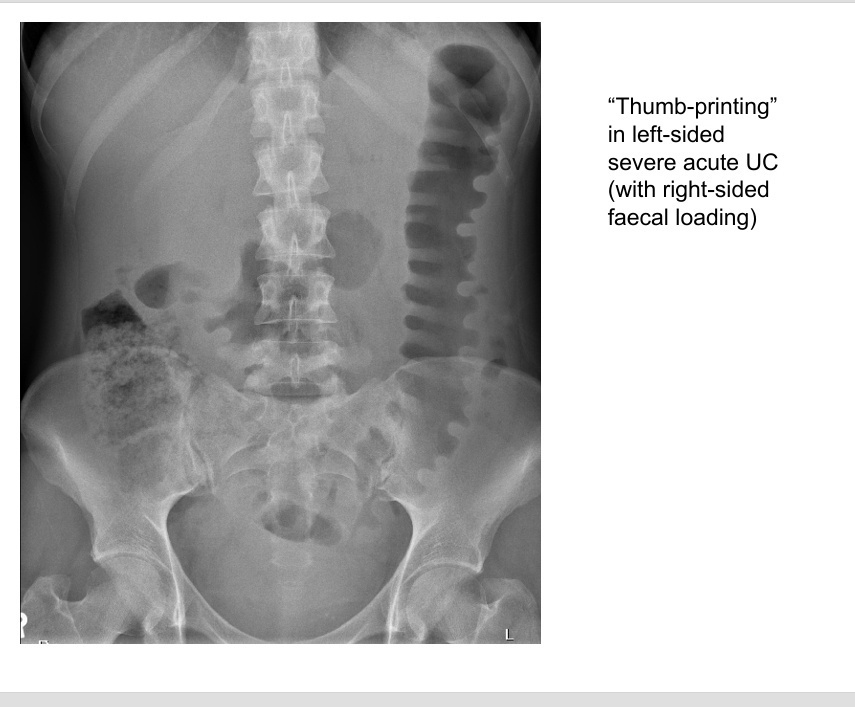

radiology?

A

• plain AXR - thumbprinting